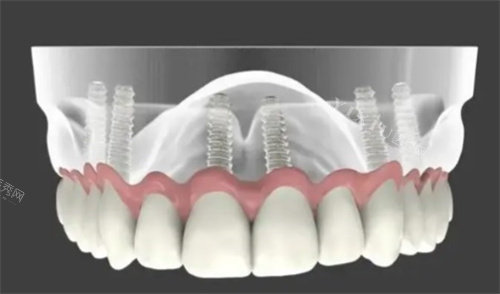

韩国进口种植牙:5200元/颗起(含基台+牙冠)